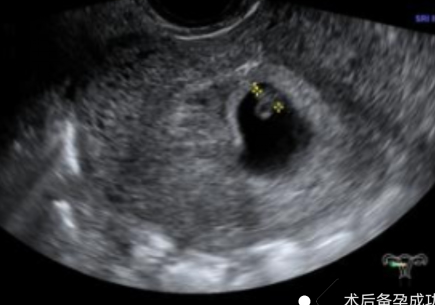

幾個月前,陳女士(化名)突發(fā)不規(guī)則陰道出血癥狀,且出血持續(xù)多天未見緩解,身體不適與生育焦慮雙重壓力下,前往我院就診,尋求專業(yè)診療方案。不規(guī)則陰道出血是婦科臨床的高頻癥狀,其背后病因復雜,可能潛藏著子宮內(nèi)膜息肉、黏膜下肌瘤、子宮內(nèi)膜增生等多種病變。若未能及時明確診斷并采取干預措施,不僅會嚴重影響患者日常生活質(zhì)量,更可能對生育功能造成不可逆的潛在威脅。針對該患者的病情,婦科胡菊英副主任帶領婦科團隊展開全面評估,最終確定宮腔鏡手術為最佳診療方案。該技術無需開刀,可經(jīng)人體自然腔道進入2025-11-10

-